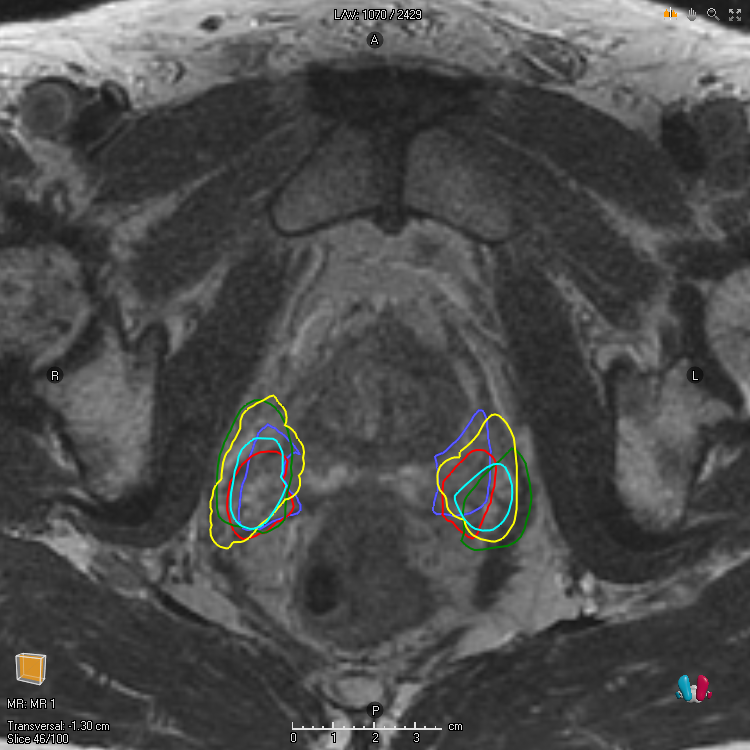

For a noisy segmentation L𝐿L, that is, a random variable taking values in 𝒮𝒮\mathcal{S}, m𝑚m can be taken to be the exact marginal success probability m(ω)=𝔼[L(ω)],ωΩformulae-sequence𝑚𝜔𝔼delimited-[]𝐿𝜔𝜔Ωm(\omega)=\mathbb{E}[L(\omega)],\;\omega\in\Omega. Such marginal functions are important in theory but can rarely be obtained in practice. Alternative choices of marginal functions include finite sample approximations, that is, point-wise averages over finite observations of L𝐿L, and estimates of 𝔼[L]𝔼delimited-[]𝐿\mathbb{E}[L] according to a single annotator [15, 11, 31, 16, 17]. These choices of m𝑚m are important because they are sometimes used for training machine learning models. Finally, note that A𝔼[L](s)=𝔼[AL(s)]subscriptA𝔼delimited-[]𝐿𝑠𝔼delimited-[]subscriptA𝐿𝑠\mathrm{A}_{\mathbb{E}[L]}(s)=\mathbb{E}[\mathrm{A}_{L}(s)] and 𝔼[AL(s)]𝔼delimited-[]subscriptA𝐿𝑠\mathbb{E}[\mathrm{A}_{L}(s)] is a common alternative way of specifying the metric. For Dice, this sort of relationship does not hold in general D𝔼[L](s)𝔼[DL(s)]subscriptD𝔼delimited-[]𝐿𝑠𝔼delimited-[]subscriptD𝐿𝑠\mathrm{D}_{\mathbb{E}[L]}(s)\not=\mathbb{E}[\mathrm{D}_{L}(s)]. However, it does hold that D𝔼[L](s)=𝔼[DL(s)]subscriptD𝔼delimited-[]𝐿𝑠𝔼delimited-[]subscriptD𝐿𝑠\mathrm{D}_{\mathbb{E}[L]}(s)=\mathbb{E}[\mathrm{D}_{L}(s)] when the volume of the noisy labels is constant Var[L1]=0Vardelimited-[]subscriptdelimited-∥∥𝐿10\text{Var}[\lVert L\rVert_{1}]=0, and it holds approximately D𝔼[L](s)𝔼[DL(s)]subscriptD𝔼delimited-[]𝐿𝑠𝔼delimited-[]subscriptD𝐿𝑠\mathrm{D}_{\mathbb{E}[L]}(s)\approx\mathbb{E}[\mathrm{D}_{L}(s)] when the variance of the volume of the noisy labels is small Var[L1]0Vardelimited-[]subscriptdelimited-∥∥𝐿10\text{Var}[\lVert L\rVert_{1}]\approx 0, which is often the case in medical image segmentation applications. Examples of observations of a particular L𝐿L for a couple of different target structures are depicted in Figure 1.

Figure 1: To the left is Urinary bladder and to the right is Neurovascular bundles for one patient in the Gold Atlas data [25]. Each line is associated with the boundary of a segmentation produced by a particular annotator. The screenshots are taken with RayStation 12A (RaySearch Laboratories AB, Stockholm Sweden).